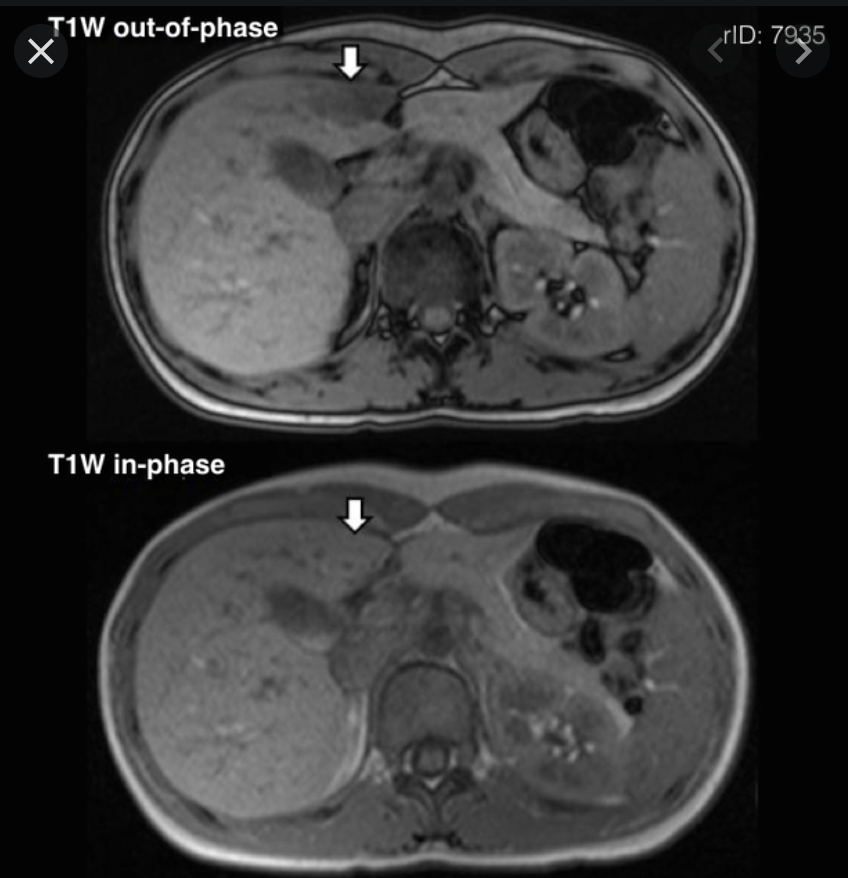

Ix: How MR in/out works.

Ix: when water & fat protons are in the same MR voxel the fat/water signals are summed in in-phase, subtracted in out-of-phase.